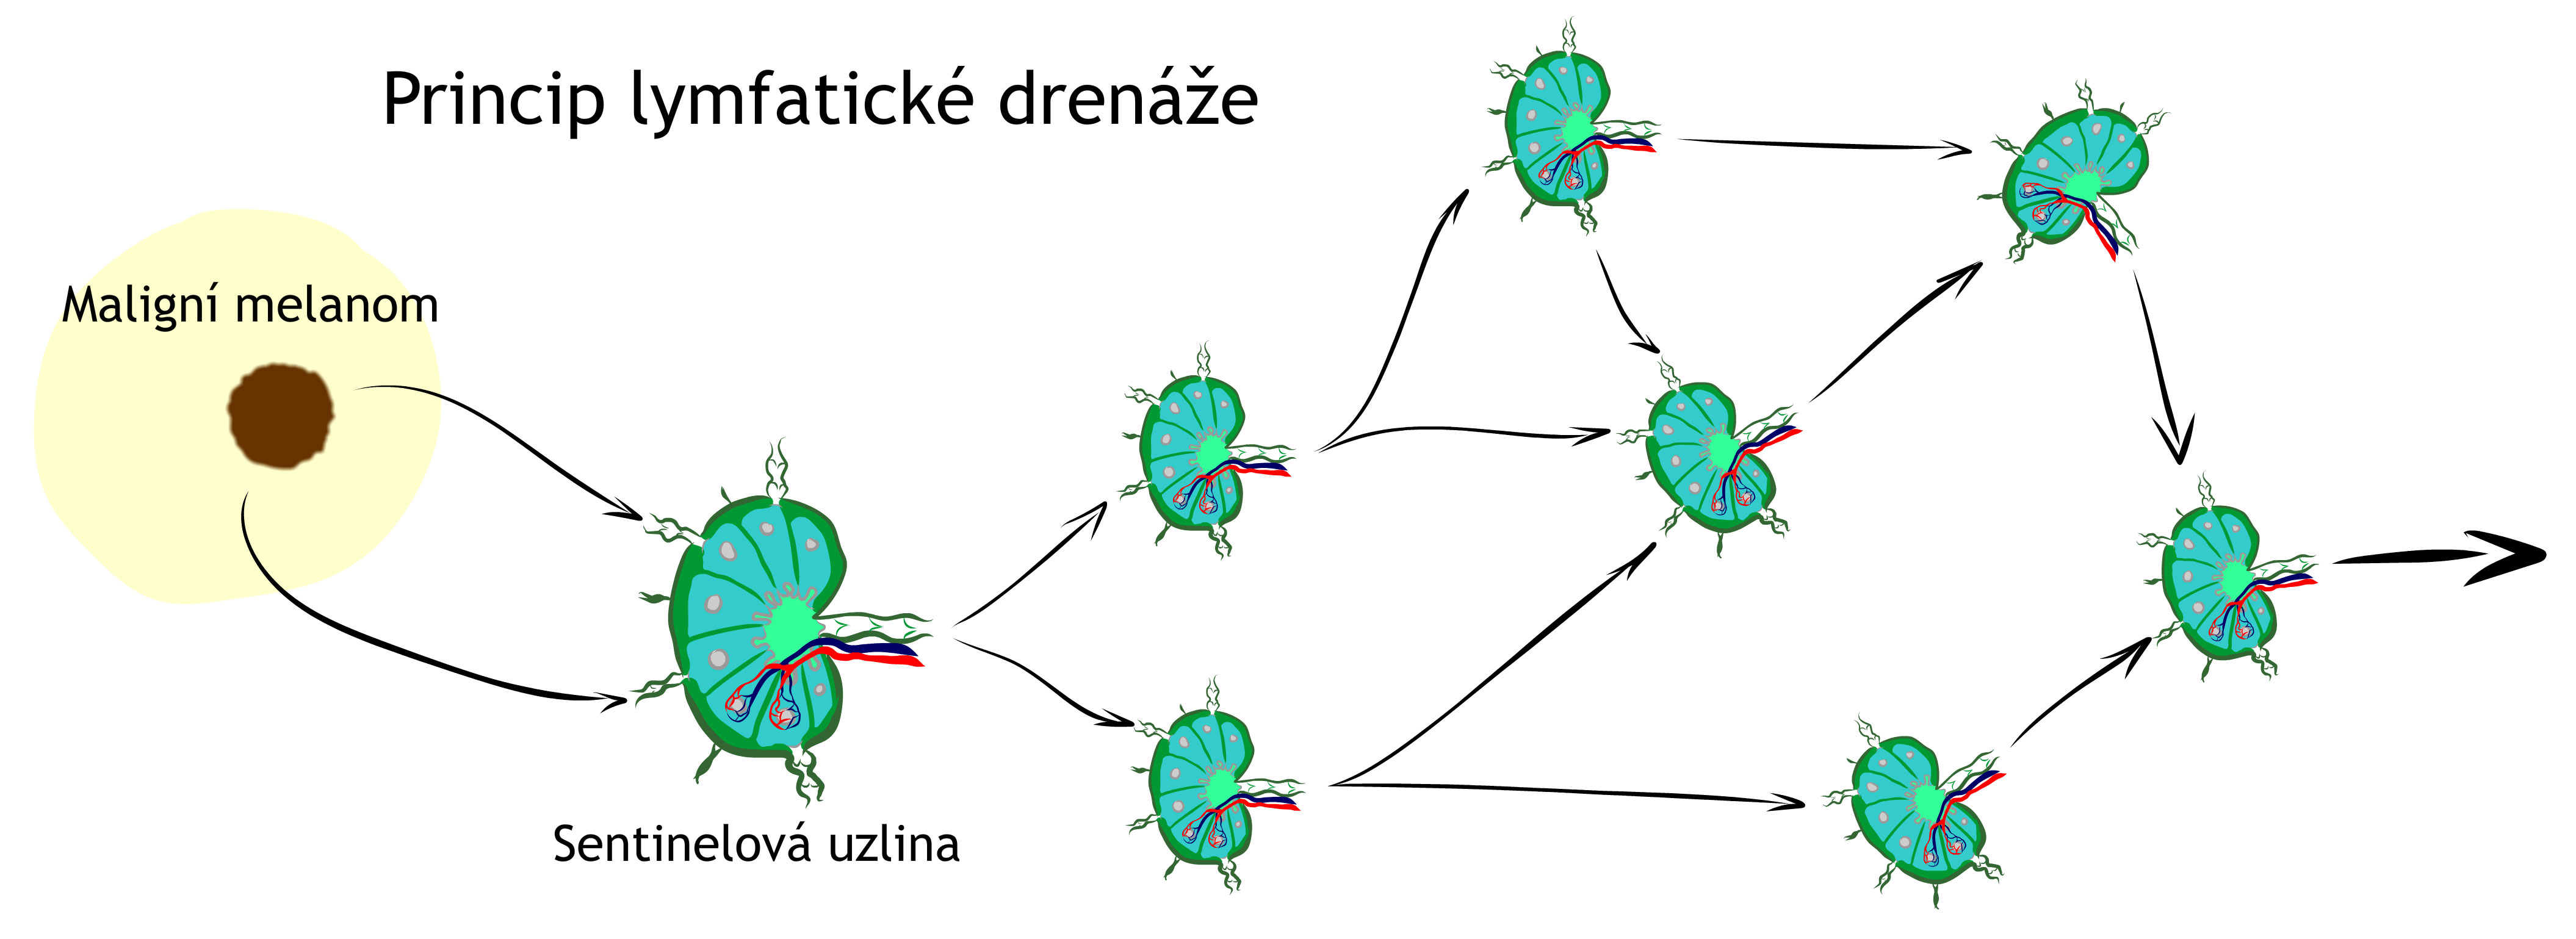

Pokud je nález vážnější, lékaři často doporučí ostranění tzv. „sentinelové (obranné) uzliny“, což je první mízní uzlina na cestě od tumoru, do které by se případné nádorové buňky mohly rozšířit. Tato uzlina je histologicky vyšetřena a je zjištěno, zda již maligní melanom do sentinelové uzliny nějaké metastázy neuvolnil.

V některých případech – pokud je riziko návratu nemoci vyšší (například metastazování melanomu do sentinelové uzliny) – může být doporučena další následná (adjuvantní) léčba: